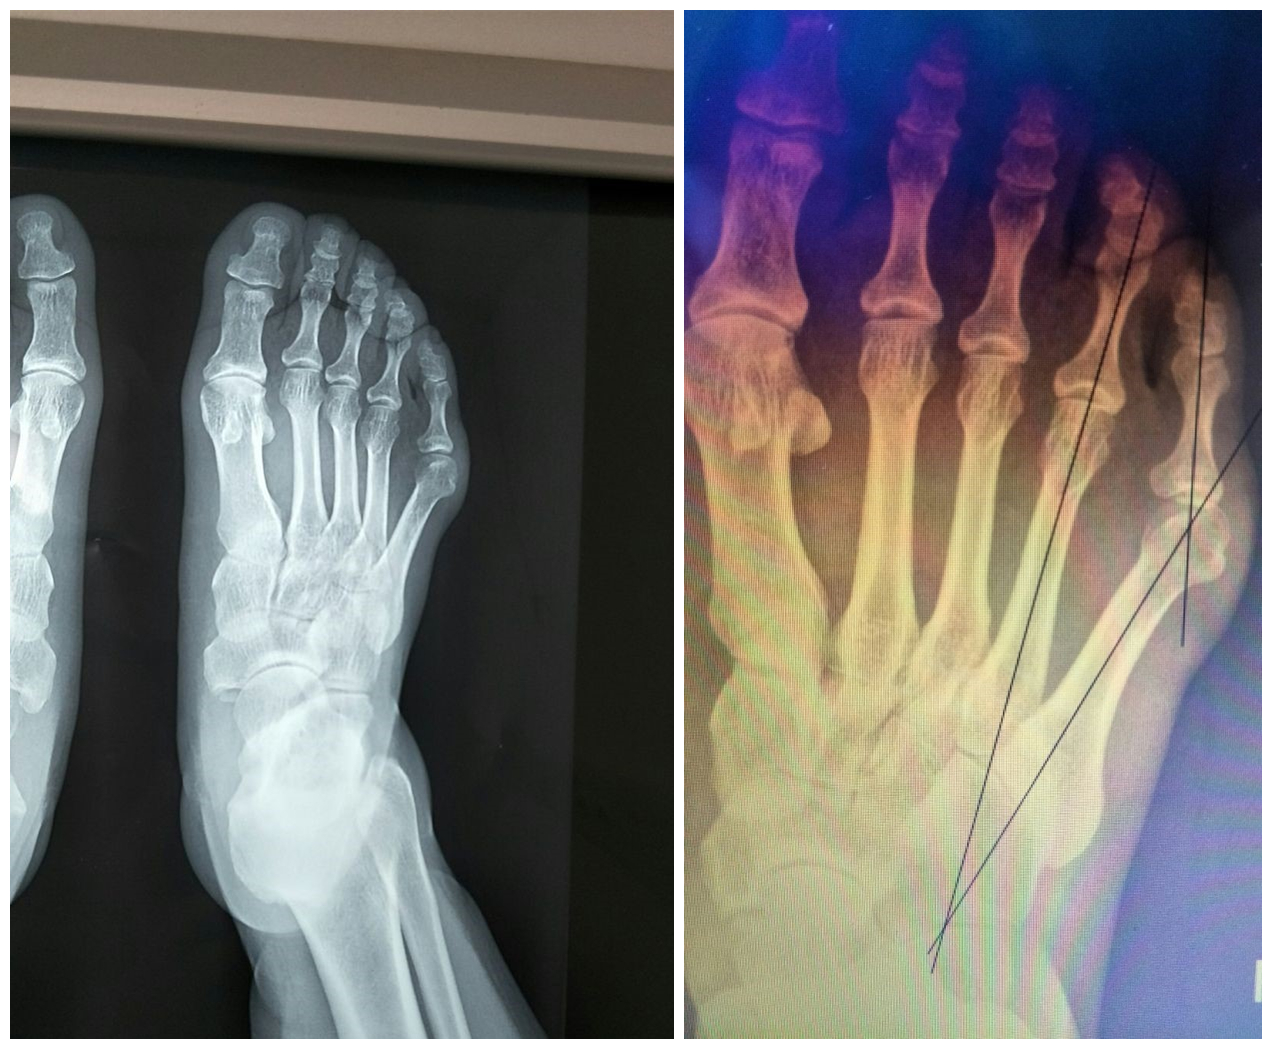

X 5 4 5 20° 20° III

X 5 4 5 20° 20°